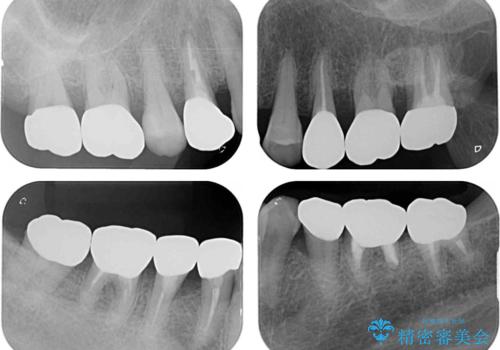

全ての奥歯の銀歯をセラミックに メタルフリー治療

- 奥歯に装着されている銀歯を全て外したいとのことで来院された患者様です。

土台に含まれている金属も含め、奥歯の金属は全て除去し、オールセラミッククラウンやセラミックインレーにて治療することとしました。